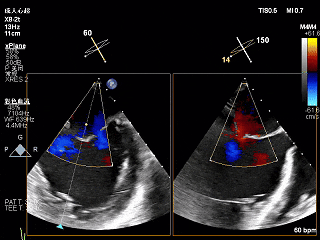

术前Bicom切面

术前X-Plane

3D-ZOOM 彩色多普勒显示反流主要来源于2区